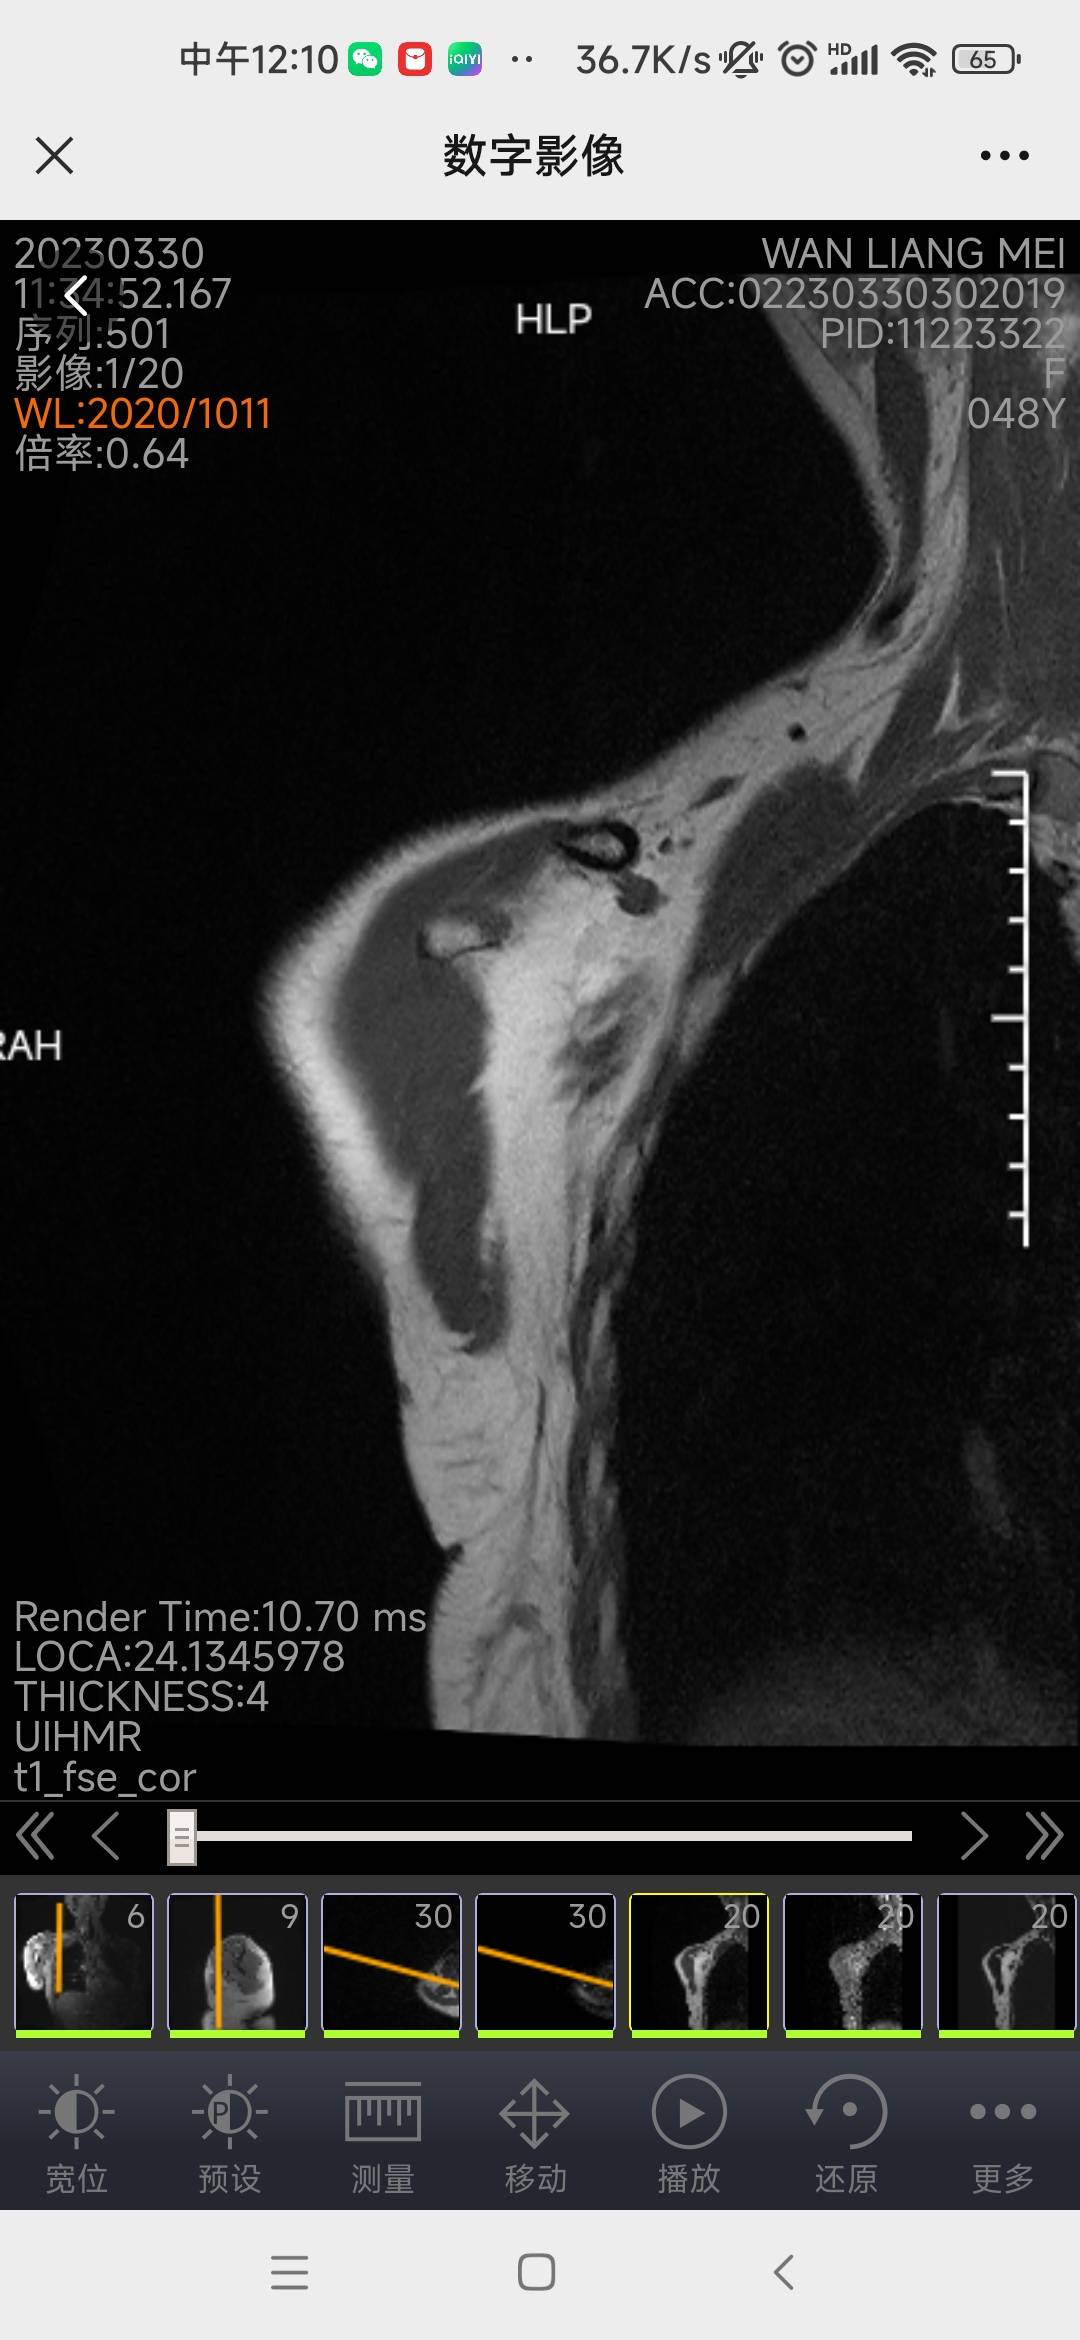

最好让影像医生看下